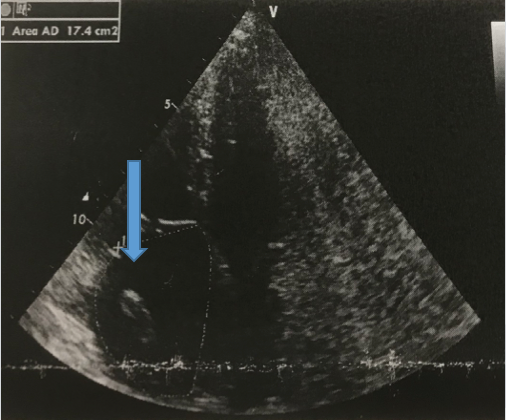

A detecção de um trombo em movimento na realização de um ecocardiograma é um evento raro. Relata-se o caso de uma paciente feminina, 66 anos, admitida com quadro de choque e submetida a realização de ultrassonografia à beira de leito, visualizando trombo saindo da veia cava para átrio direito e passando pela valva tricúspide até o ventrículo direito, direcionando com maior efetividade ao diagnostico e tratamento de tromboembolismo pulmonar. Demonstra-se a importância do conhecimento pratico e acessibilidade da ultrassonografia à beira de leito no atendimento de Emergência do Hospital Universitário Professor Polydoro Ernani de São Thiago.